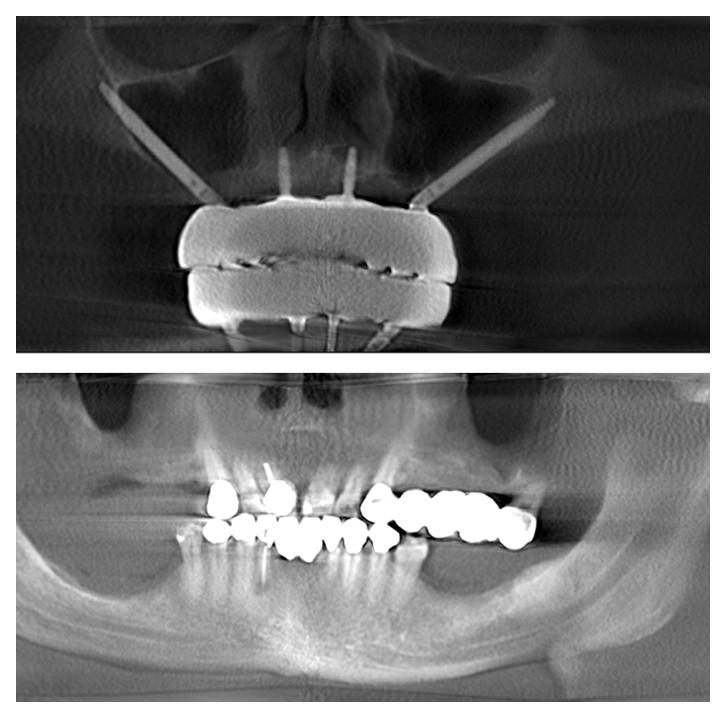

- Immediate Teeth Placement: One of the biggest advantages of Zygomatic and Pterygoid Implants is that they allow for same-day placement of teeth. Unlike traditional methods that can take up to a year, our no-bone implant solutions can give you a full set of permanent teeth in just a few hours. This means you walk out with a new smile on the same day as your surgery.

- Zygomatic and Pterygoid Implants: A Faster Solution: Traditional dental implant methods often require extensive bone grafting and a lengthy healing period, sometimes taking up to a year before final teeth are placed. Zygomatic and Pterygoid Implants bypass the need for bone grafts by anchoring the implants in the cheekbone and pterygoid plate, allowing for immediate loading of teeth. This not only shortens the treatment time dramatically but also provides a solution for patients who were previously told they weren’t candidates for implants due to severe bone loss.

Before and After

Zygomatic Implants